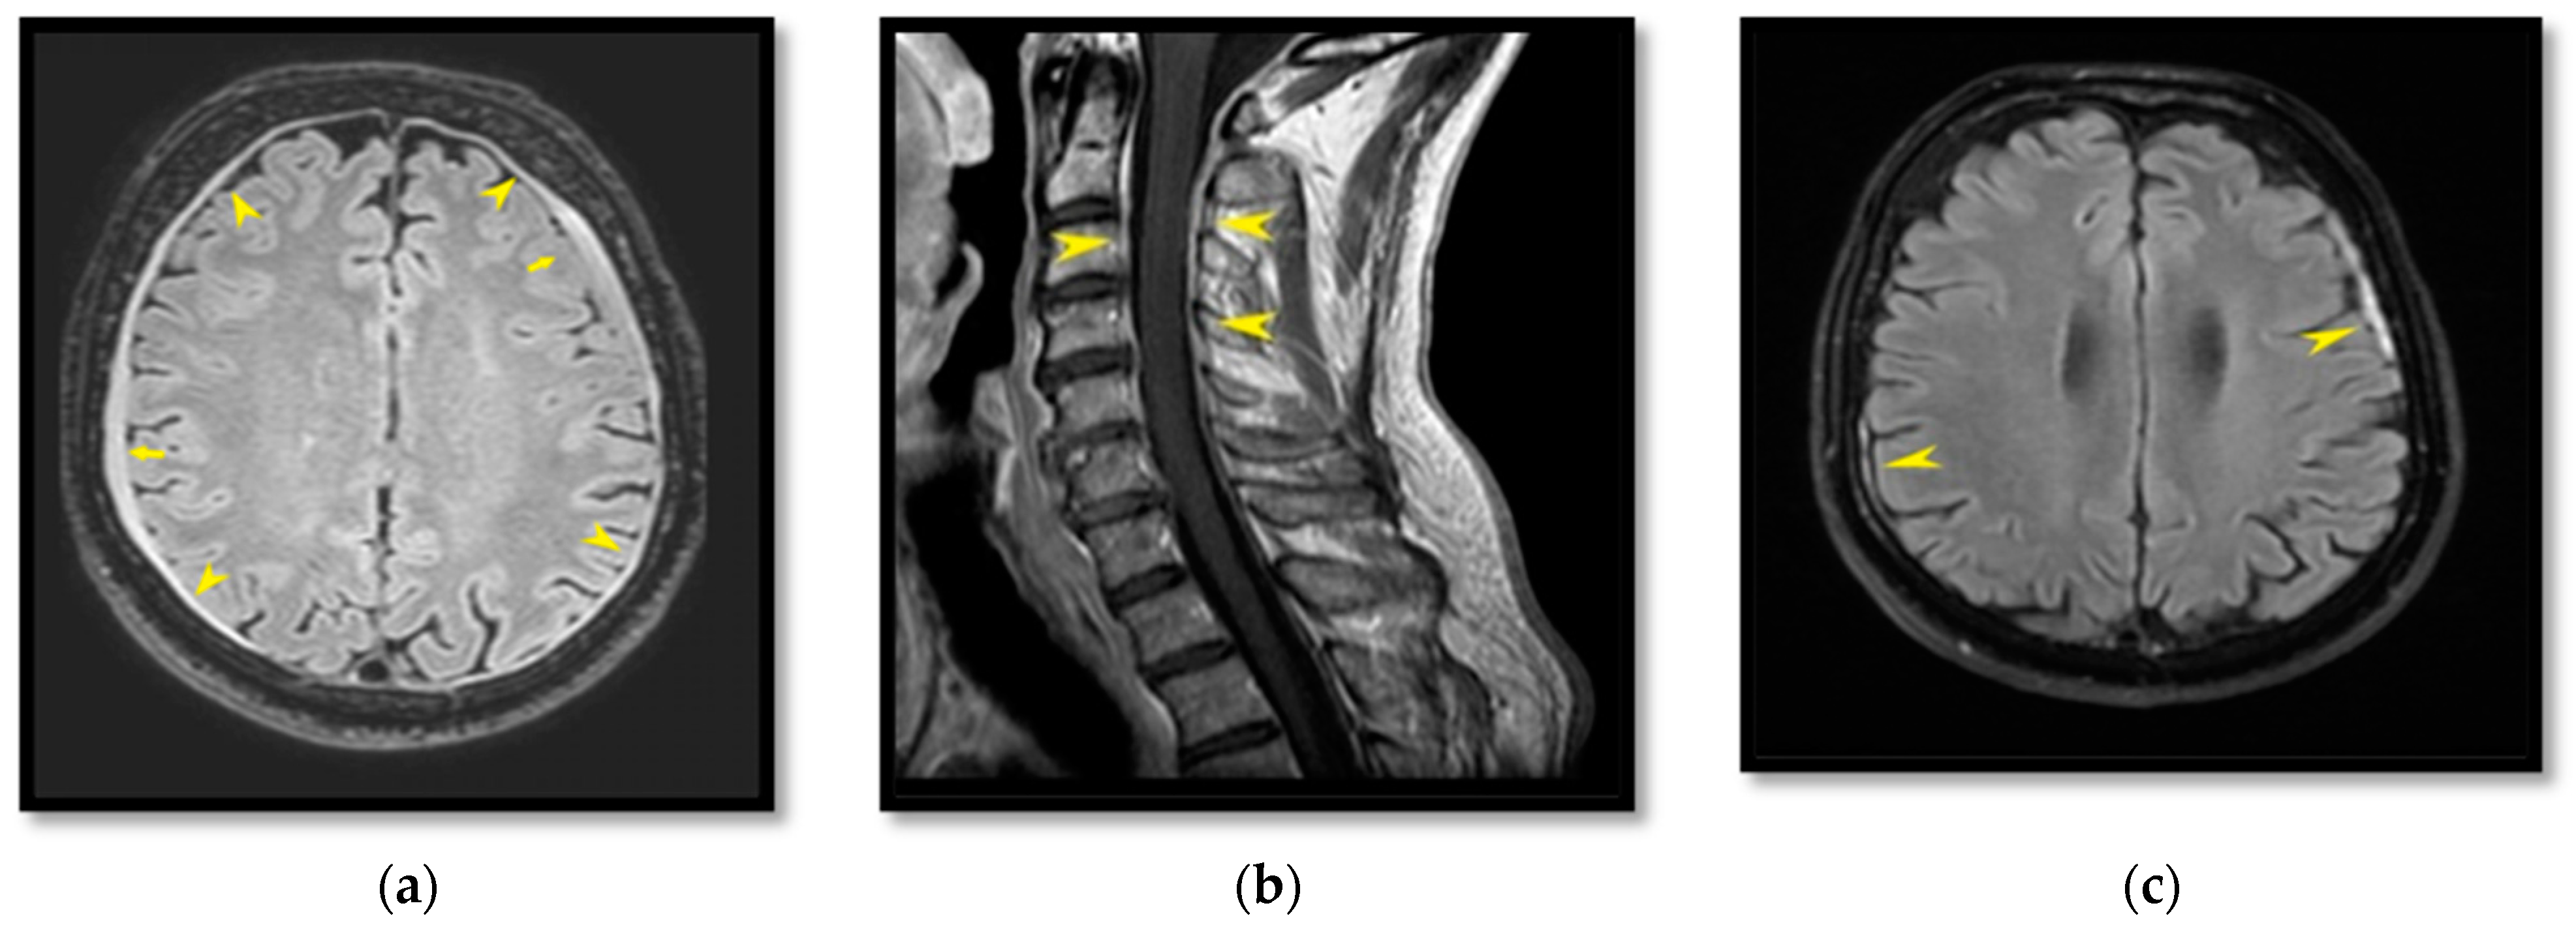

2.1. Patient I